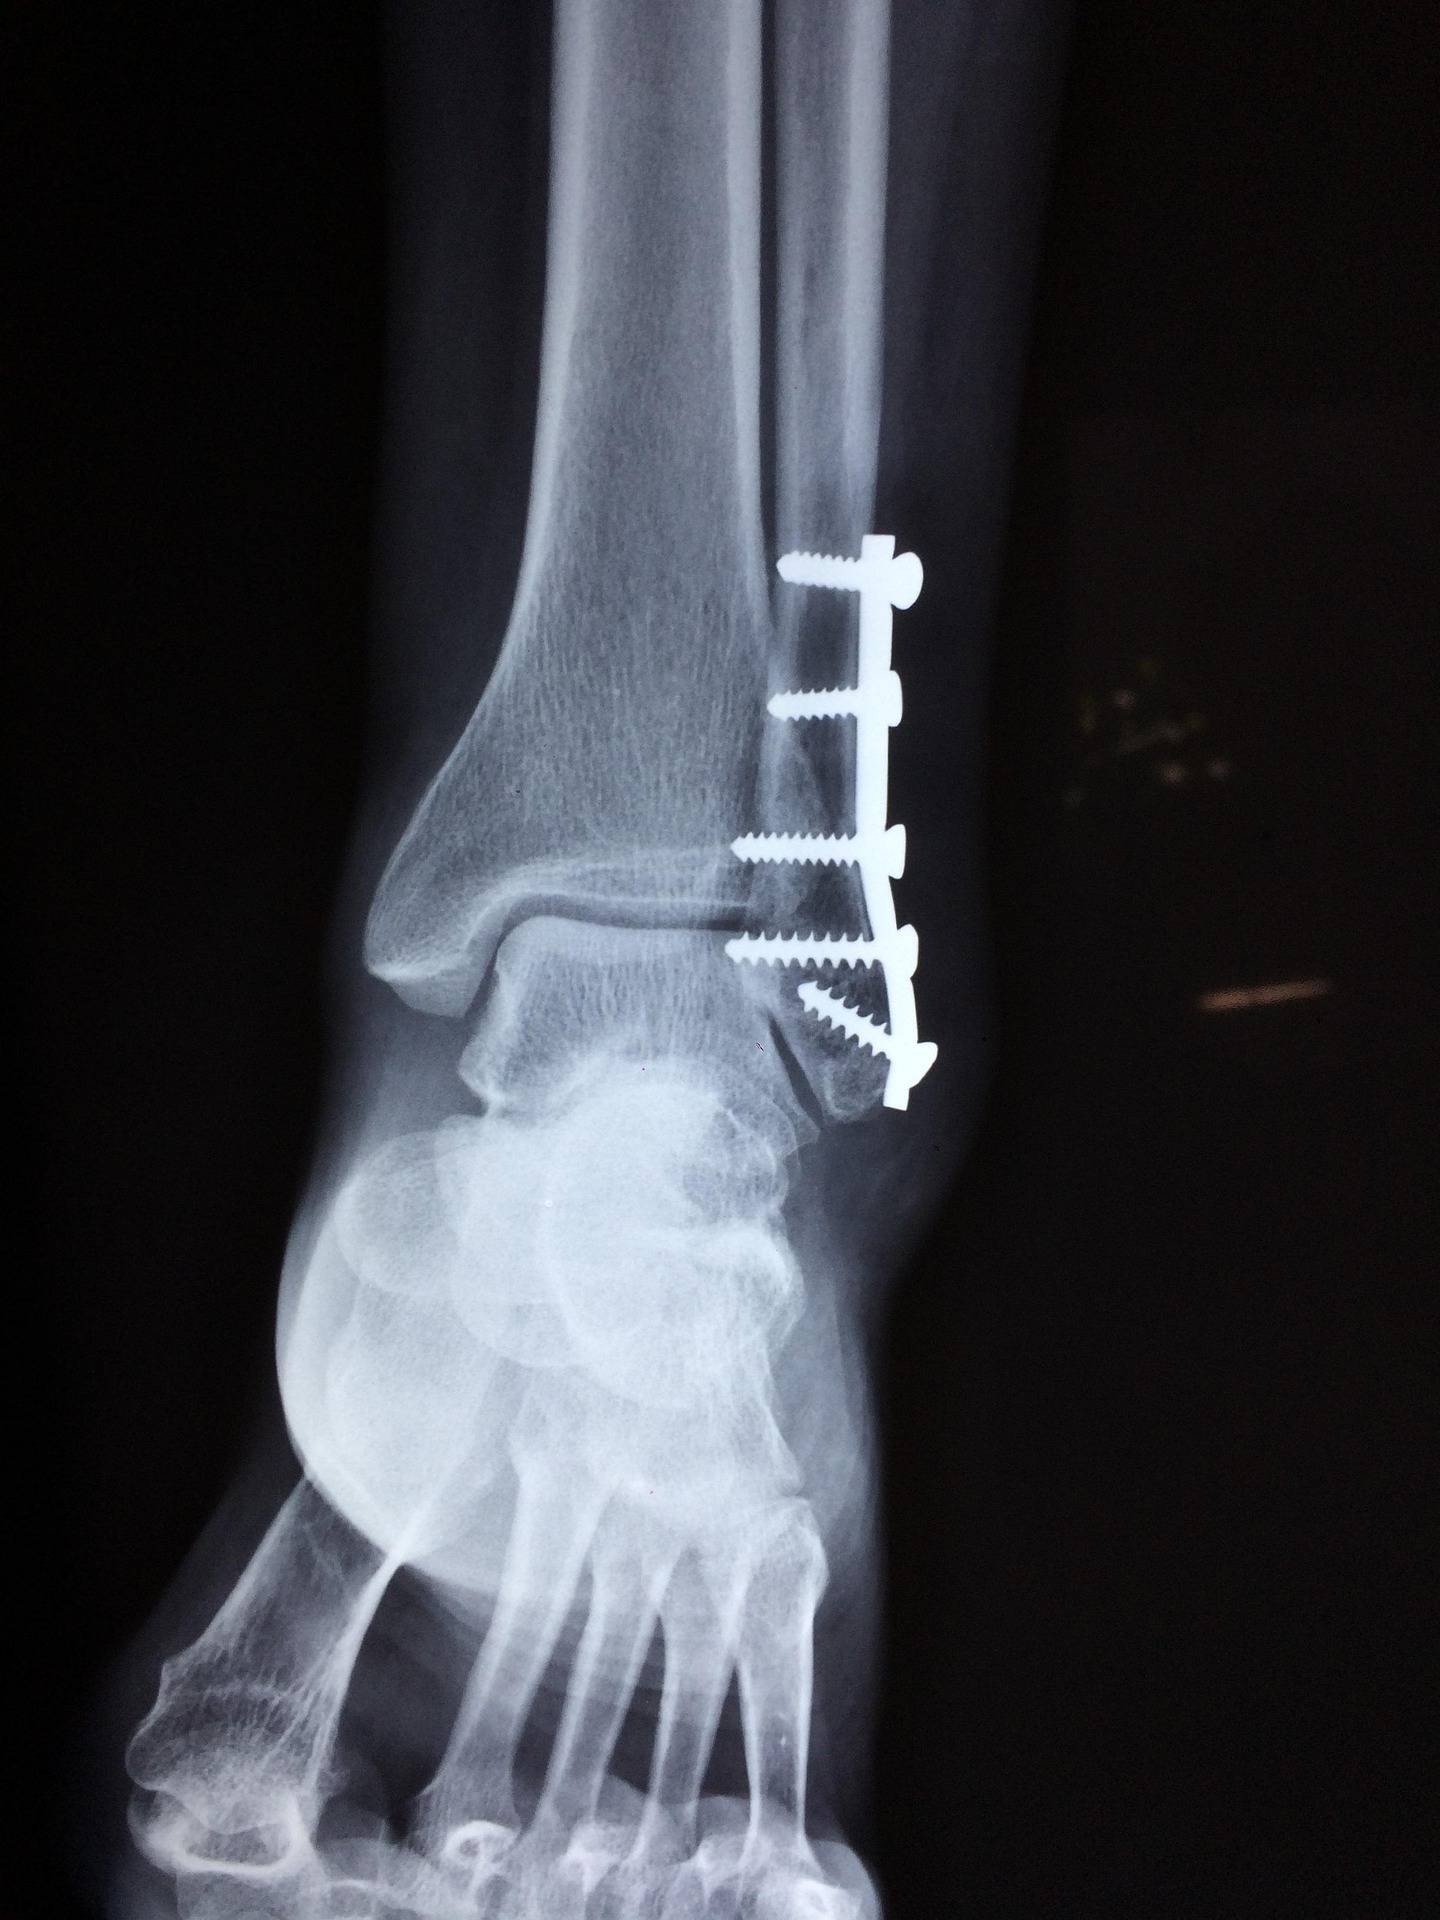

Az utóbbi napokban 10-20 százalékkal nőtt a betegek száma a Debreceni Egyetem Traumatológiai Klinikáján a jeges, csúszós utak miatt. A sérültek többsége elesés vagy elcsúszás következtében szenvedett végtagtörést, ficamokat vagy rándulásokat, miközben a mentők egyetlen nap alatt több mint 200 feladatot láttak el a vármegyében. Bár a hétvégére némi enyhülés várható, az előrejelzések szerint a jövő hét elején visszatér a kemény fagy. A szakemberek óvatosságra intik a közlekedőket, mivel a csapadék és a fagyos éjszakák miatt továbbra is fennáll a balesetveszély a járdákon és az utakon.